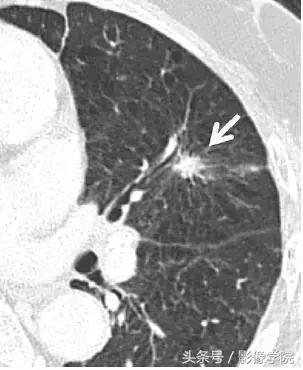

6、毛刺状结节

图 6 左肺上叶层厚 1 mm 的 CT 横断面图像,显示一个可疑的实性毛刺状结节(箭头)。手术证实为浸润性腺癌。